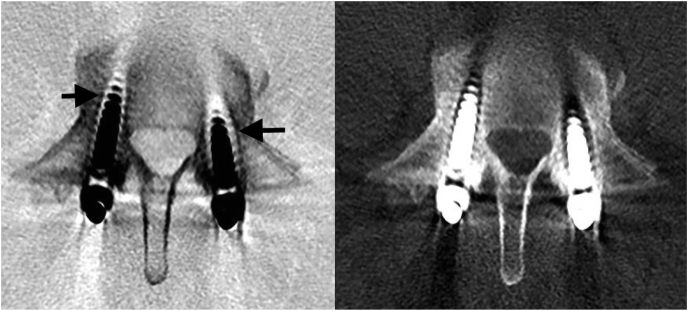

Fig. 2.

Inversion greyscale CT (left) and conventional CT image (right). There is loosening of both pedicle screws (worse on the right – as you look at the image (black arrows). Again on the inverted images the number of correct classifications increased.